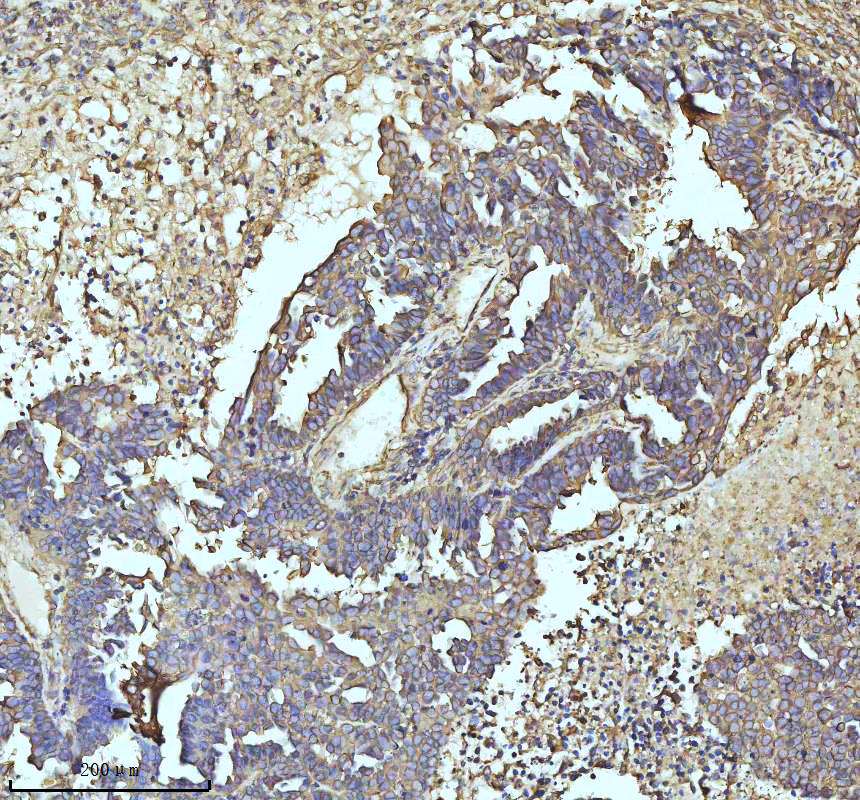

IHC analysis of beta I Tubulin/TUBB1 using anti-beta I Tubulin/TUBB1 antibody (BM3878) .

beta I Tubulin/TUBB1 was detected in a paraffin-embedded section of human ovarian cancer tissue. The tissue section was incubated with rabbit anti-beta I Tubulin/TUBB1 Antibody (BM3878) at a dilution of 1:200 and developed using HRP Conjugated Rabbit IgG Super Vision Assay Kit (Catalog # SV0002) with DAB (Catalog # AR1027) as the chromogen.